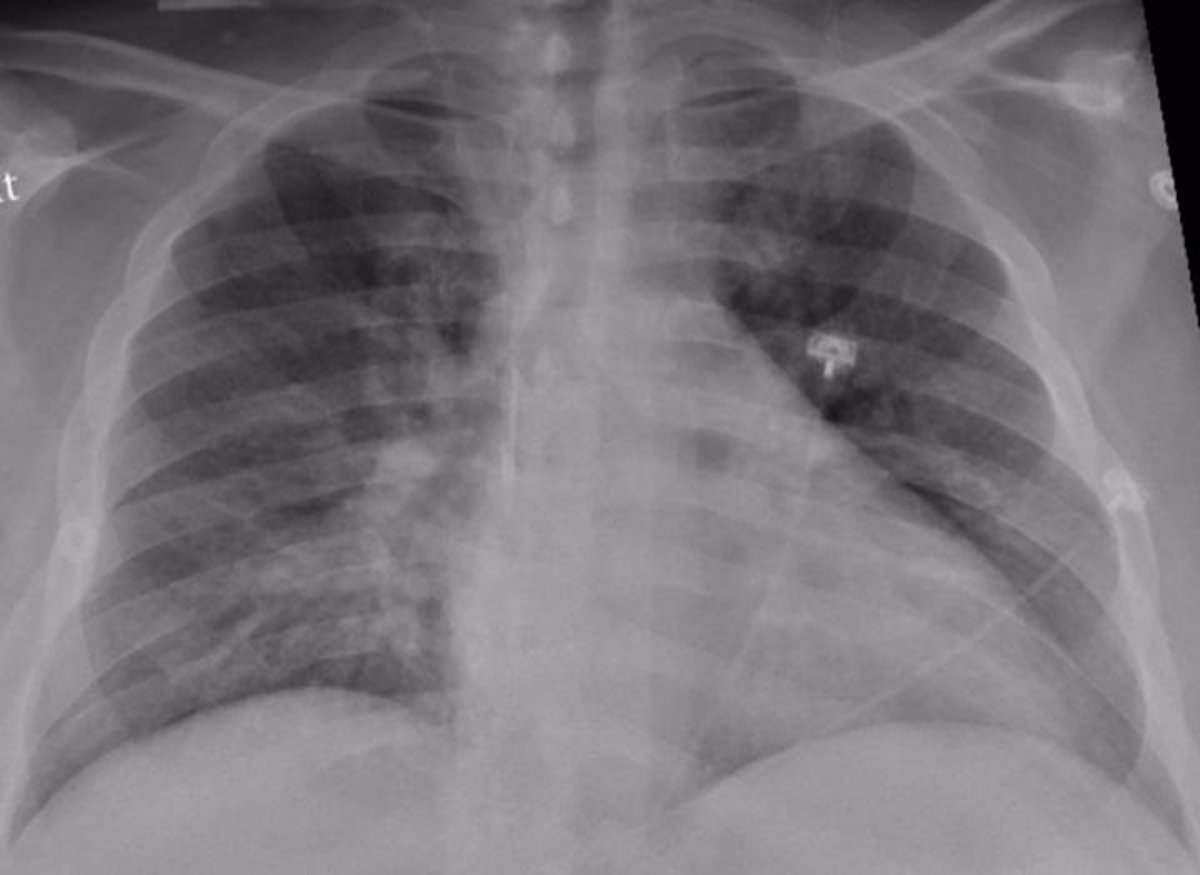

Sin lugar a dudas, el Covid es una afección que afecta primeramente a los pulmones, pero sus daños no se limitan a ese órgano porque también muchos otros tales como: corazón, riñones y cerebro, lo que sin lugar a dudas de ser persistentes en el tiempo, puede causar daños mayores a los mismos y complicaciones.

Esta persistencia del Covid, pueden incluir secuelas en los órganos mencionados, manifestándose problemas tales como: problemas respiratorios por mucho tiempo, problemas cardíacos, afecciones renales crónicas, accidente cerebrovascular, síndrome de Guillain-Barré (parálisis temporal) e incluso síndrome inflamatorio multisistémico donde los órganos y tejidos se inflaman de manera grave